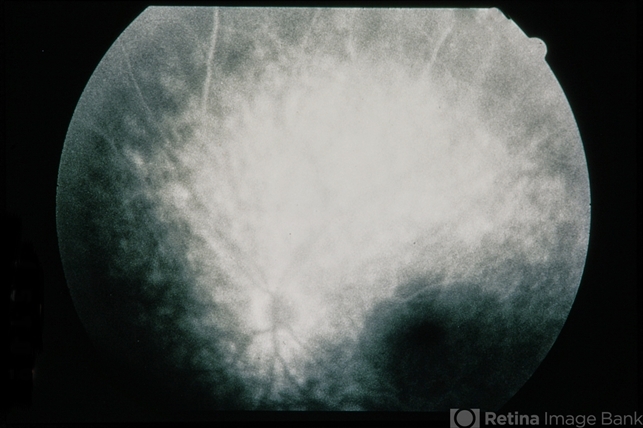

Plaquenil Toxicity

60-year-old female with plaquenil toxicity.